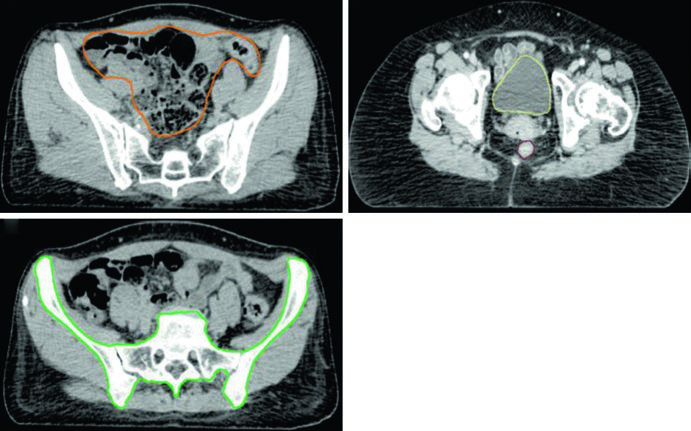

Organs at risk (OAR) in planning include bowel, bladder, rectum, and femoral heads. In patients receiving concurrent adjuvant chemotherapy, pelvic bone marrow should be included as an OAR — this technique has been shown to reduce hematologic toxicity risk.

| Bowel | Outermost loops of bowel from L4-5 interspace to the sigmoid flexure, including sigmoid colon and ascending/descending colon in the pelvis | V35 Gy < 35%; V45 Gy < 200 cc |

| Rectum | Outer rectal wall from sigmoid flexure to the anus | V45 Gy < 50% |

| Bladder | Outer bladder wall | V45 Gy < 35% |

| Bone Marrow | Pelvic bones (os coxae, L5 vertebral body, entire sacrum, acetabulae, proximal femora). Superior: superior border of L5 or iliac crest. Inferior: ischial tuberosities | V10 Gy < 90%; V20 Gy < 75%; V40 Gy < 37% |

| Femoral Heads | Entire femoral head excluding femoral neck | V30 Gy < 15%; V50 Gy < 5% |

The bowel contour deserves particular attention: it should include the entire peritoneal space encompassing the bowel, with superoinferior boundaries extending 1.5 cm superior to the caudal aspect of the PTV and inferiorly to the rectosigmoid junction. In the anteroposterior direction, the bowel extends from the anterior abdominal wall to the most posterior extent of bowel. Bilateral bowel edges serve as left-right boundaries.